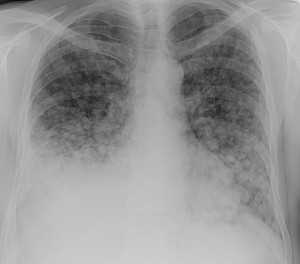

Как выглядят метастазы в легких на рентгене? Слева — узловые образования у пациента с раком яичка. Справа - метастазы рака яичников гематогенного характера с выраженным опухолевым лимфангиитом (обратите внимание на деформированный сетчатый, линейный характер легочного рисунка).

Лимфогенные метастазы на рентгене и КТ выглядят как множественные мелкие очаги с диссеминированным распространением, локализованные в междольковых перегородках, в плевральных листках. Вокруг можно видеть характерную картину ракового лимфангиита. Кроме того, практически всегда выявляются патологически измененные и увеличенные лимфатические узлы средостения. Лимфогенное метастазирование необходимо дифференцировать с милиарным туберкулезом, саркоидозом. Иногда это требует привлечения Второго мнения.

Лимфогенные метастазы проявляются увеличением лимфатических узлов средостения в сочетании с мелкоочаговой диссеминацией с очагами до 2-3 мм в диаметре вблизи плевры и в междольковых перегородках, а также по ходу бронхов и сосудистых пучков.